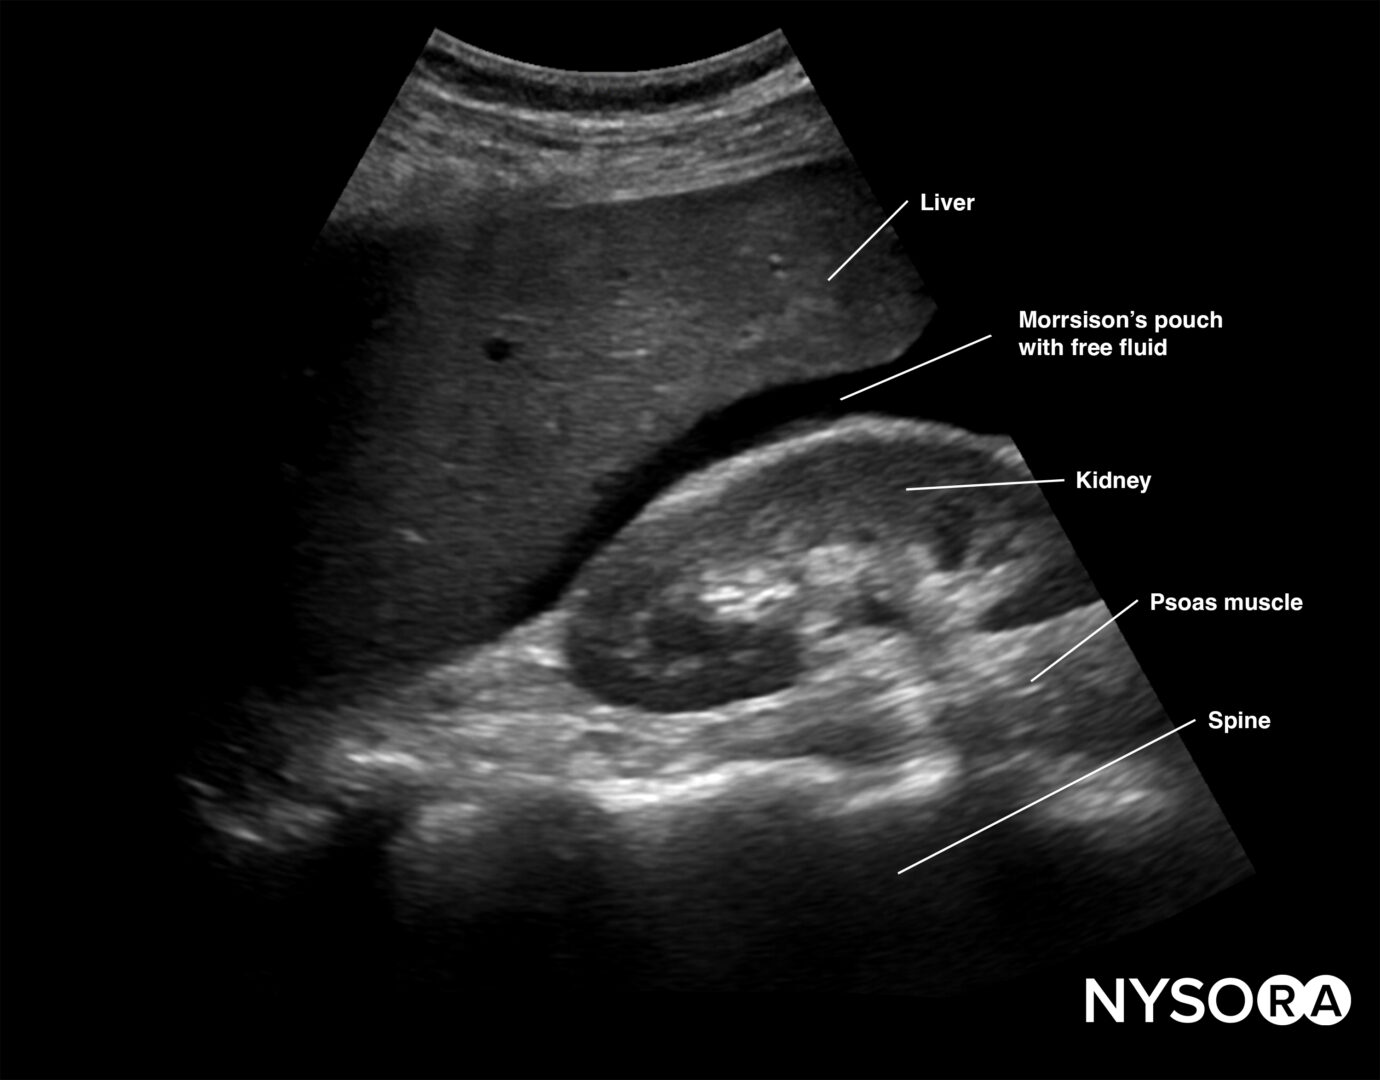

Right upper quadrant (RUQ)

Detects free fluid in the right thorax and abdomen.

- Position the transducer between the mid- and posterior axillary lines at the level of the xiphoid process, with the orientation marker facing the patient’s head.

- Scan caudally until you visualize the liver and the kidney; fluid usually collects between the liver and the kidney, i.e., Morrison’s pouch.

- Structures of interest: lung, diaphragm, liver, kidney, Morrison’s pouch (virtual space between liver and kidney)

Free right intraperitoneal fluid collects between the liver and the kidney (Morrison’s pouch). If intrathoracic free fluid is present, it can be identified above the diaphragm.

Free intraperitoneal fluid is often found between the liver and the kidney, i.e., Morrison’s pouch.